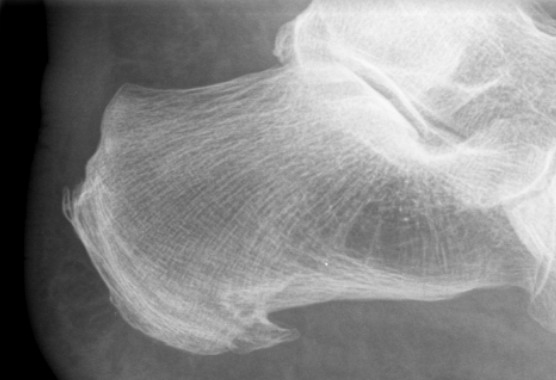

ausgeprägter dorsaler und asymptomatischer plantarer Fersensporn![]() |

||||||